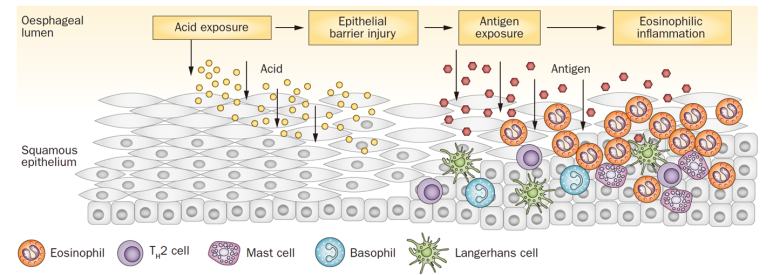

현재 명확하게 제시된 메커니즘은 없지만 nature에 발표된 리뷰에 따르면 산 노출로 식도의 epithelial barier injury가 발생하면 해당 부위에 음식, aeroallergen이 epithelial barrier를 가로질러 식도 내로 들어가게 됩니다. 이렇게 들어간 외부 allergen은 면역세포(Th2 cell, Mast cell, 호산구 등)에 의해 염증반응이 증가합니다.

이 염증반응에 의해 혈관의 신생합성이 증가하여 근육층이 두꺼워지고 섬유화가 진행되어 식도의 운동성을 저하시키고 내강이 좁아지는 담보이기 때문에 음식통과를 위한 경로가 적어집니다.